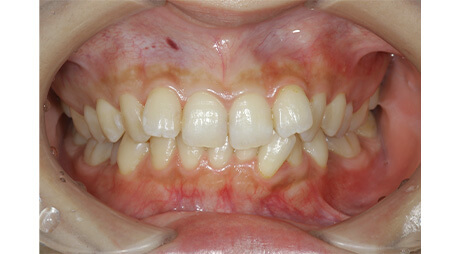

上の前歯の古い被せ物を治したいと言うことで来院されました。上下の前歯は少しガタガタになっており、奥歯には古い金属の詰め物が見られます。

上の前歯の被せ物が長い期間保つようにするためには、下の前歯のガタガタを整えておく必要があります。この症例くらいのガタガタであれば、インビザラインGoを使えば短期間で綺麗に治すことができます。歯並びが整ったことで治療のモチベーションが上がり、ホワイトニングと奥歯の銀歯を全てセラミックに置き換える治療を行い、金属がない(ノンメタル)状態になりました。